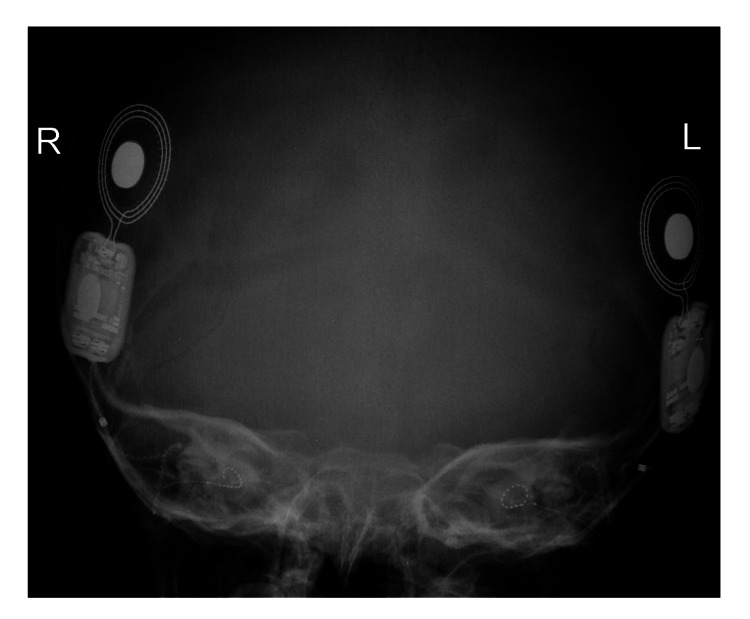

患者被 CI 委员会确定为双侧植入的候选者。 在三岁零五个月大时,进行了双侧同时人工耳蜗植入(HiRes™ Ultra #D 人工耳蜗,右 HiFocus™ SlimJ 电极和左 HiFocus™ Mid-Scala 电极,Advanced Bionics AG,加利福尼亚州,美国)。 术后 X 线显示 CI 阵列完全插入耳蜗内(图 2)。 手术后第二天开机,并给予两个 Naida CI Q70 声音处理器(Advanced Bionics AG,加利福尼亚州,美国)。

病例 2 的术后 X 线颞骨显示双耳人工耳蜗电极阵列完全插入